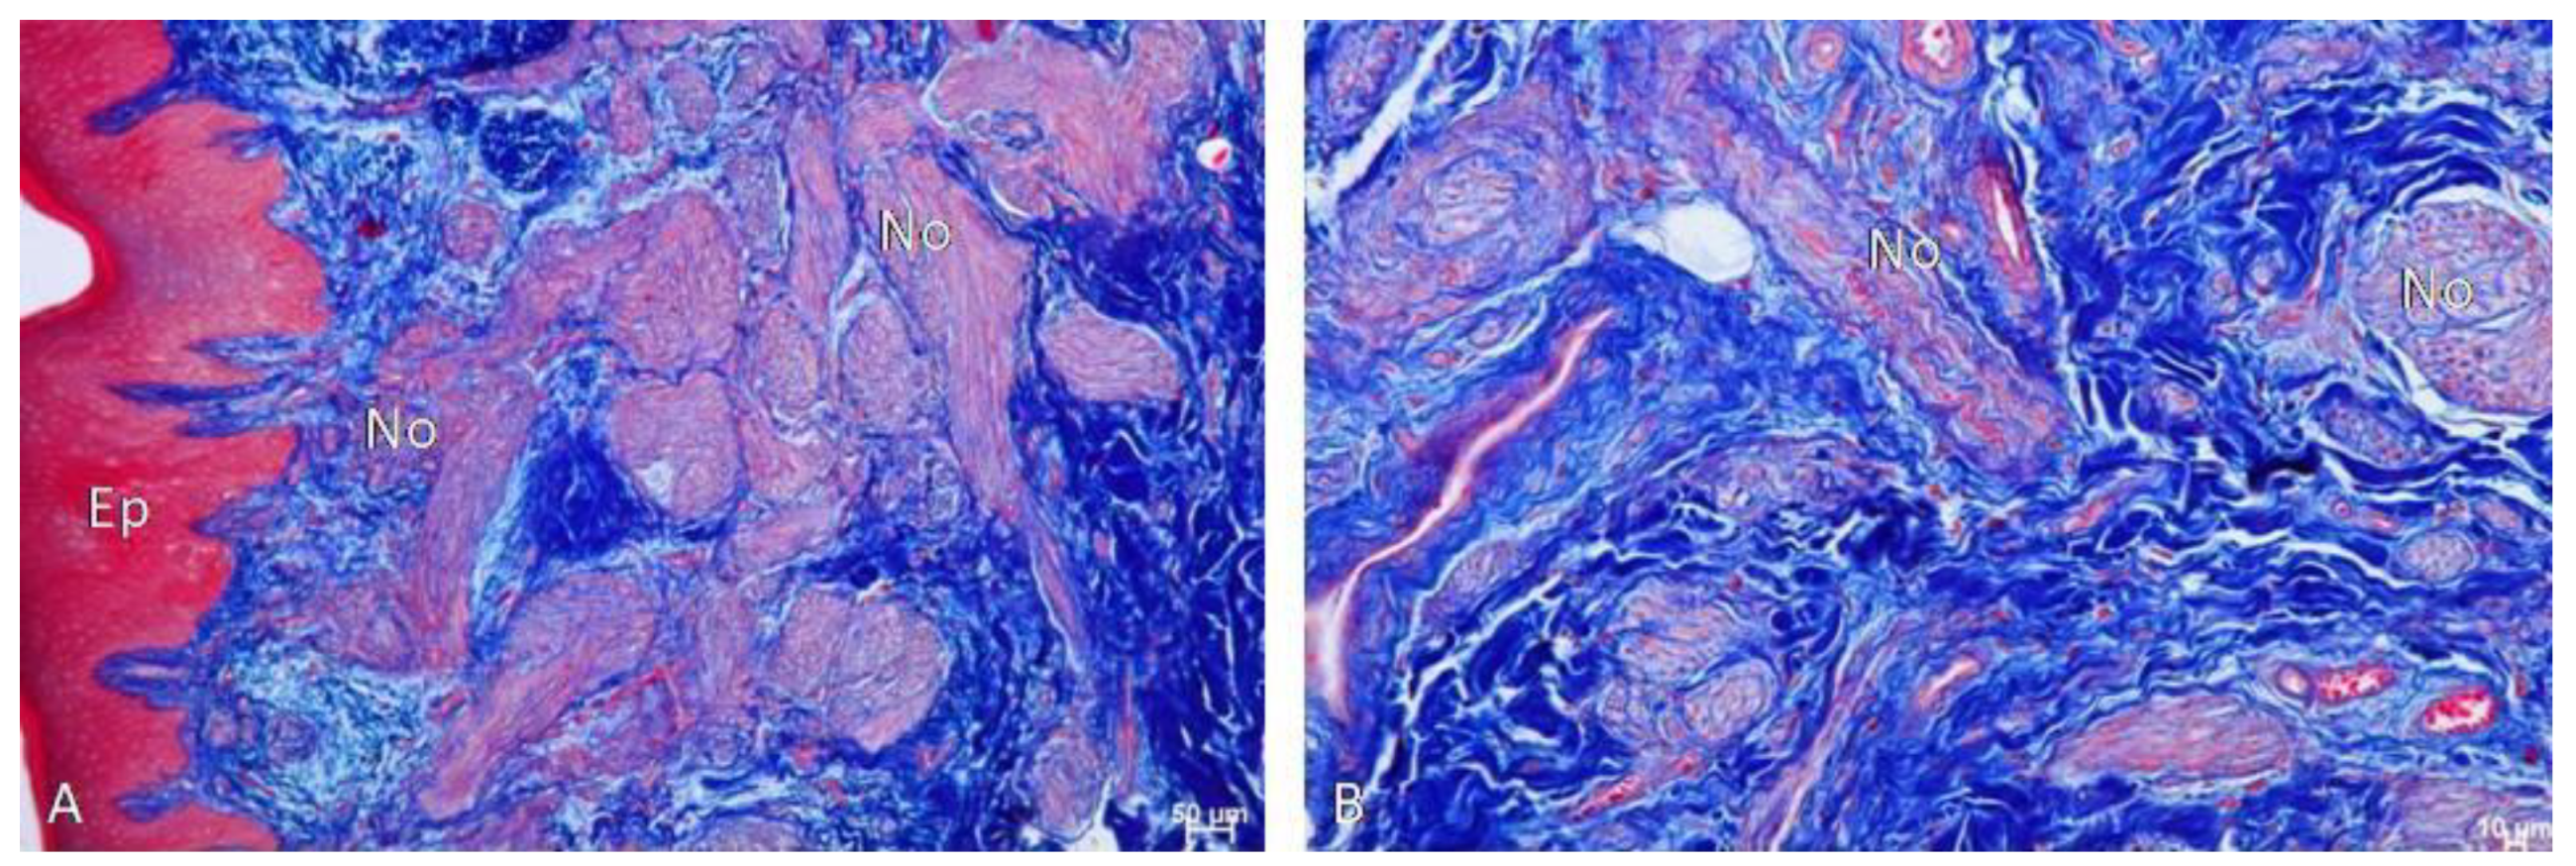

Histological Findings